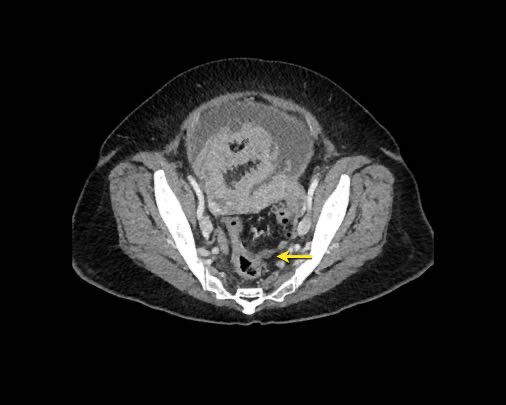

Ở vùng chậu, vị trí quan trọng nhất là túi cùng trực tràng-tử cung và trực tràng-bàng quang (túi cùng Douglas).

Tuy nhiên, vòm bàng quang phía trên và ống niệu rốn được ngăn cách với khoang bụng bởi một lớp phúc mạc thành, tạo thành đích tiềm năng cho các tế bào khối u.

Đặc biệt khi bàng quang đầy, các tổn thương di căn phúc mạc có thể được quan sát thấy ở phía trước bàng quang, áp sát thành bụng trước.